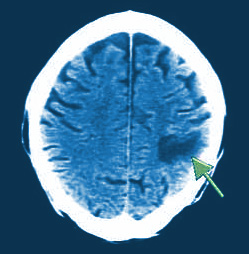

CT是基于同样的原理与常规的X射线。 X射线是由身体的不同部分吸收不同。 骨吸收了大部分的X射线,所以头骨的图像上显示为白色。 水(在大脑中的中间脑室或充满液体的腔体)吸收小,并且出现黑色。 大脑有中等密度和出现灰色。 大多数缺血性中风是密度较小(较暗)比正常脑,而血出血是更密集,看起来是白色的CT检查。

CT扫描使用计算机和旋转X光机来创建切片的图像,或横截面,大脑的。 不同于其它技术,CT扫描(和MRI扫描)可以显示出头部的内侧,包括软组织,骨骼,脑和血管。 CT扫描通常可以显示所造成的肿瘤,血管缺陷,血液凝块和其他问题的大小和大脑异常的位置。 CT扫描确定行程是否是缺血性或出血性的主要方法。